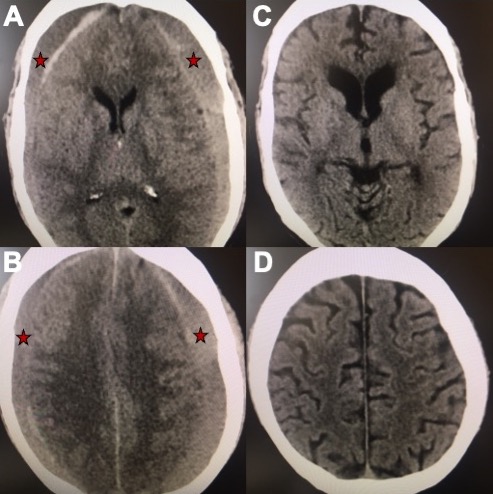

Middle Meningeal Artery Embolization – This procedure is performed in an endovascular intervention suite with the patient under sedation. The endovascular surgeon uses minimally invasive technique to enter the blood vessels in the arm or leg, advances small tubes through the arteries under x-ray guidance and navigates them to the middle meningeal artery on the side of the chronic subdural hematoma. The middle meningeal artery is located on the underside of the skull in the dura matter but also provides blood supply to the abnormal membranes that surround the hematoma and contribute to hematoma growth (see Figure 2). Under fluoroscopic guidance (low dose continuous x-rays), the surgeon delivers a specially made glue or small particles through the small tube and permanently blocks the middle meningeal artery. After the procedure, the tubes are removed and the small puncture site in the arm or leg artery is closed. In the weeks following the procedure, there is reduced bleeding from the subdural hematoma membranes and the hematoma collection slowly shrinks in size and often goes away completely over the course of several months (see Figure 3).

Figure 3. A, B) Axial views of a brain CT scan demonstrating chronic subdural hematomas on both sides of the brain compressing it inwards (red stars mark the hematoma). C, D) Axial views of a CT brain of the same chronic subdural hematoma 3 months after Middle Meningeal Artery Embolization demonstrating resolution of the chronic subdural collection on both sides.